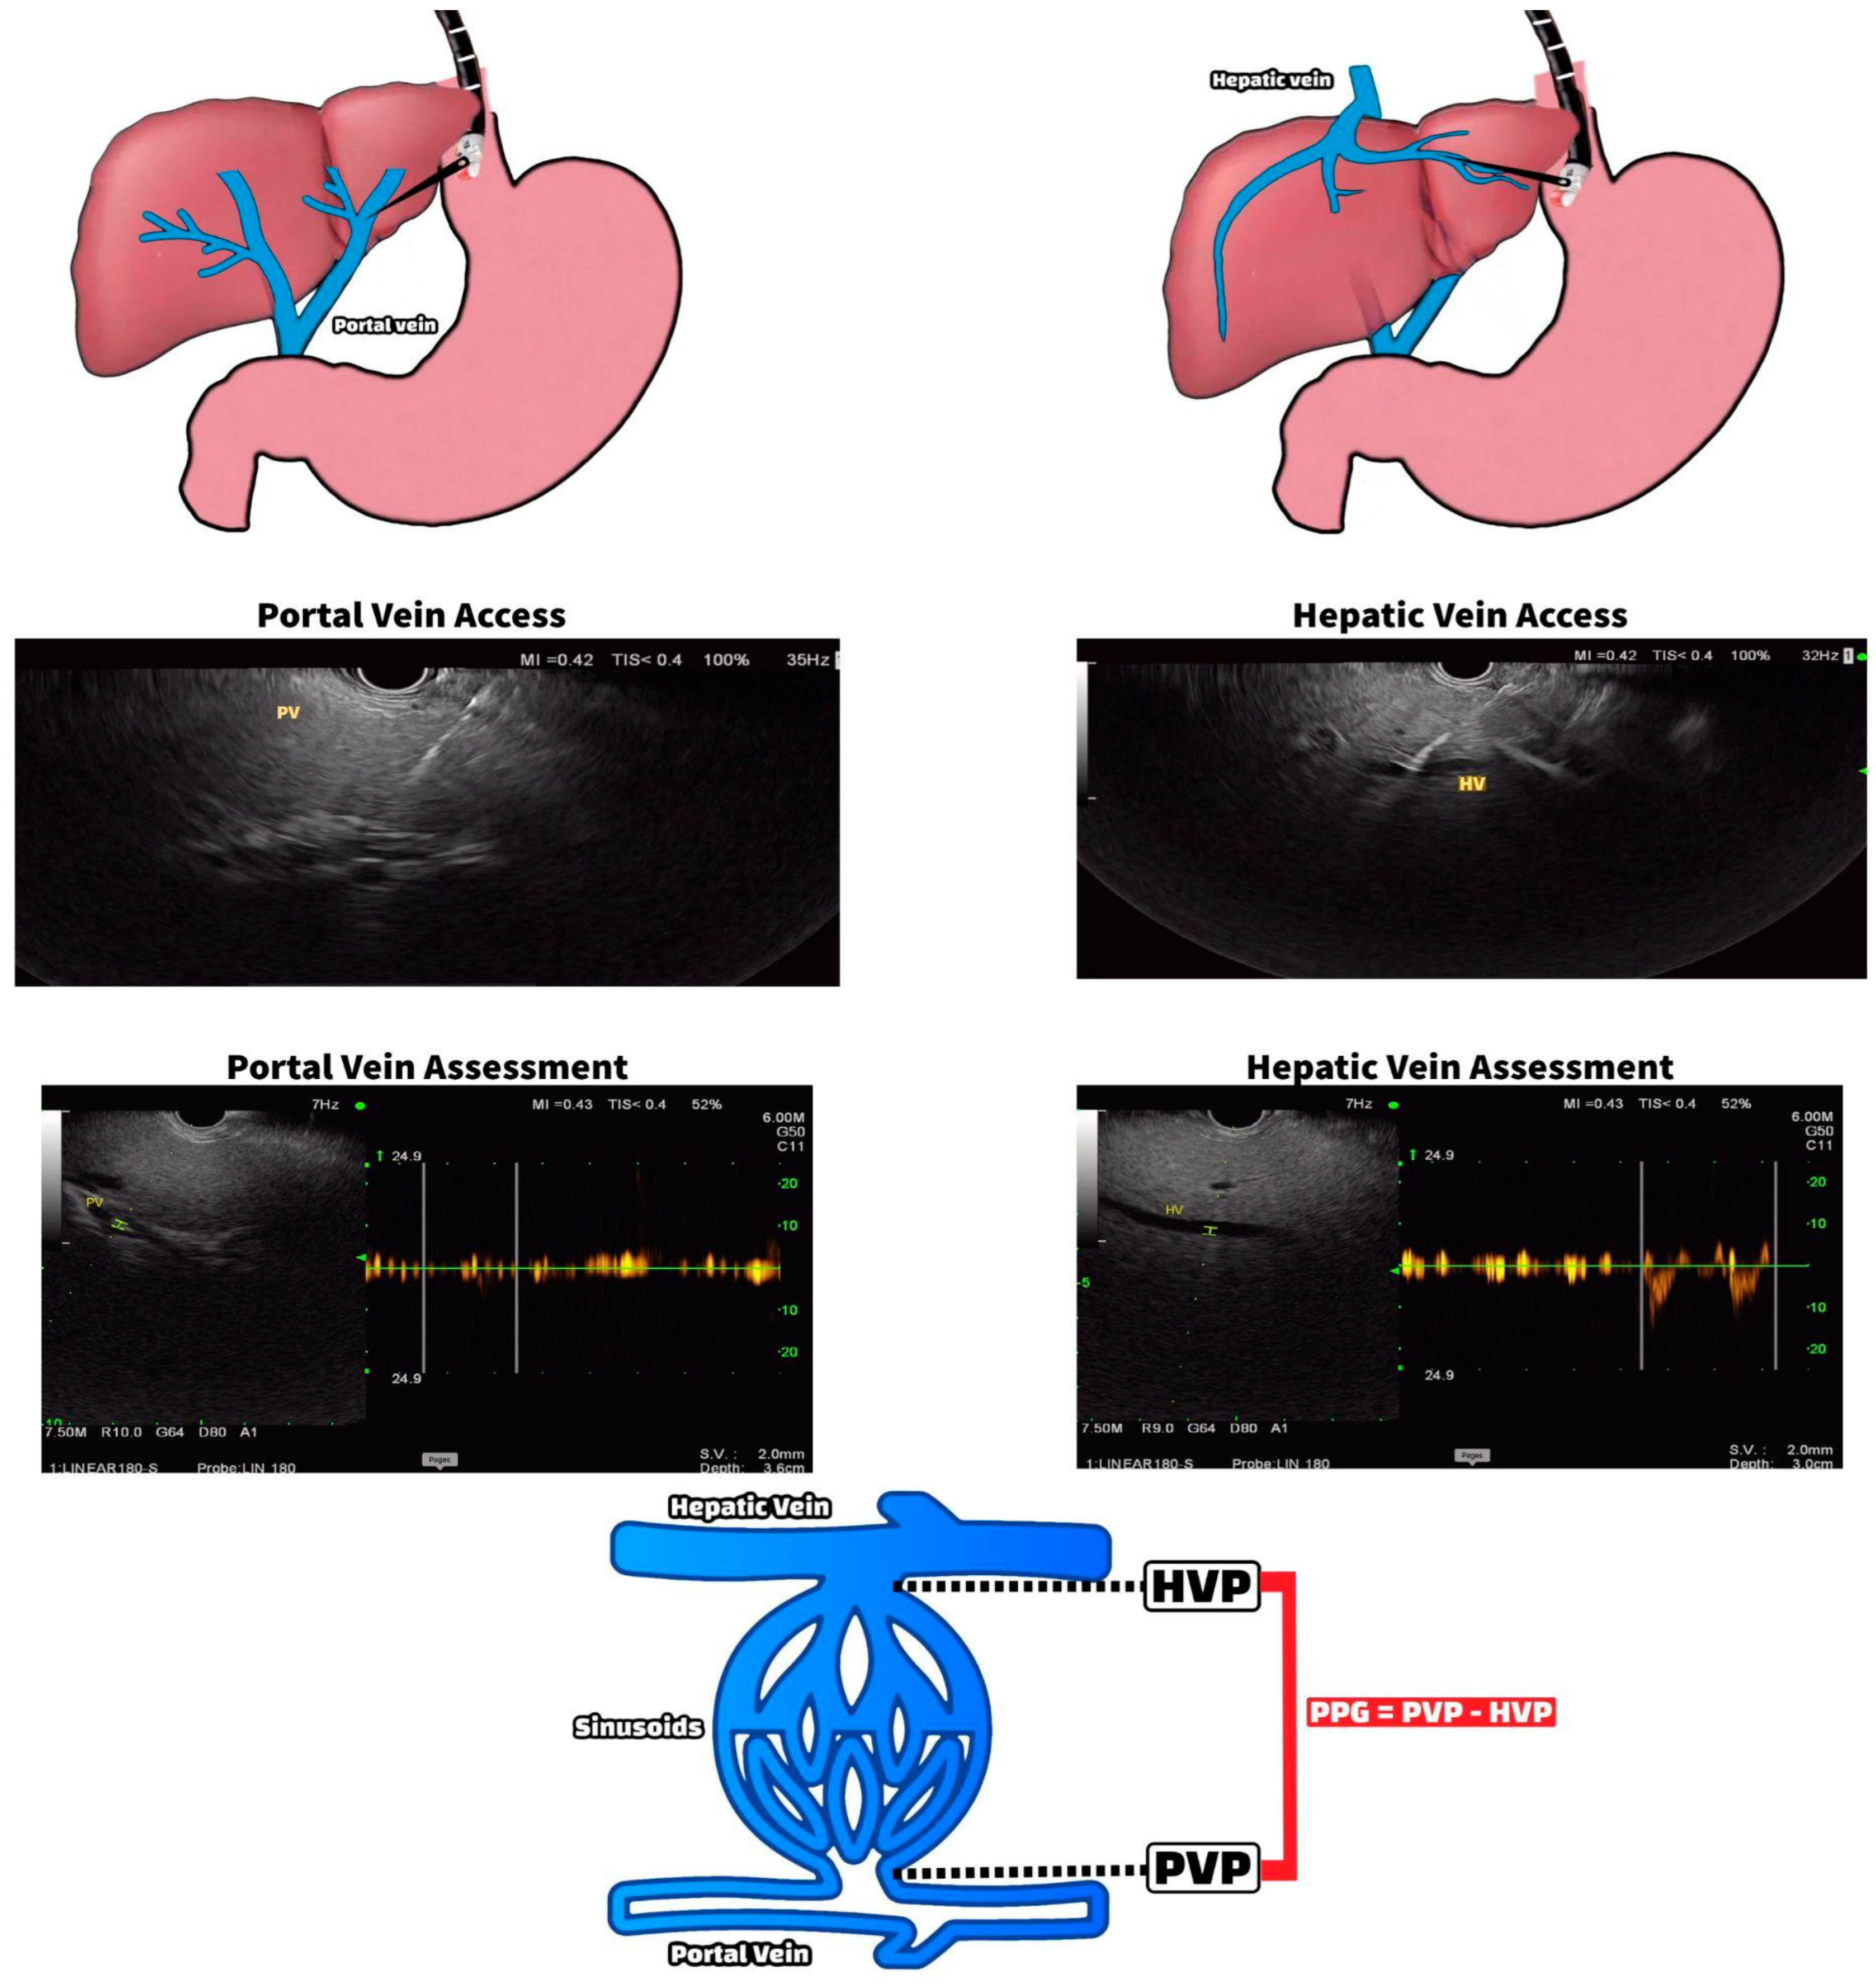

2.1.1. EUS-Guided Portal Pressure Measurement

- Bazarbashi, A.N.; Ryou, M. Portal pressure measurement: Have we come full circle? Gastrointest. Endosc. 2021, 93, 573–576. [Google Scholar] [CrossRef]

- Zhang, W.; Peng, C.; Zhang, S.; Huang, S.; Shen, S.; Xu, G.; Zhang, F.; Xiao, J.; Zhang, M.; Zhuge, Y.; et al. EUS-guided portal pressure gradient measurement in patients with acute or subacute portal hypertension. Gastrointest. Endosc. 2020, 93, 565–572. [Google Scholar] [CrossRef]

- Huang, J.Y.; Samarasena, J.B.; Tsujino, T.; Chang, K.J. EUS-guided portal pressure gradient measurement with a novel 25-gauge needle device versus standard transjugular approach: A comparison animal study. Gastrointest. Endosc. 2016, 84, 358–362. [Google Scholar] [CrossRef]

- Huang, J.Y.; Samarasena, J.B.; Tsujino, T.; Lee, J.; Hu, K.-Q.; McLaren, C.E.; Chen, W.-P.; Chang, K.J. EUS-guided portal pressure gradient measurement with a simple novel device: A human pilot study. Gastrointest. Endosc. 2016, 85, 996–1001. [Google Scholar] [CrossRef]

- Samarasena, J.B.; Huang, J.Y.; Tsujino, T.; Thieu, D.; Yu, A.; Hu, K.Q.; Lee, J.; Chang, K.J. EUS-guided portal pressure gradient measurement with a simple novel device: A human pilot study. VideoGIE 2018, 3, 361–363. [Google Scholar] [CrossRef]

- Choi, A.Y.; Kolb, J.; Shah, S.; Chahine, A.; Hashimoto, R.; Patel, A.; Tsujino, T.; Huang, J.; Hu, K.; Chang, K.; et al. Endoscopic ultrasound-guided portal pressure gradient with liver biopsy: 6 years of endo-hepatology in practice. J. Gastroenterol. Hepatol. 2022, 37, 1373–1379. [Google Scholar] [CrossRef]